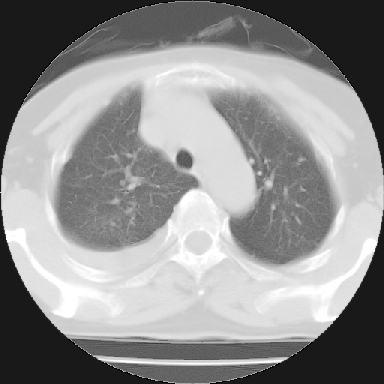

以下是引用苯小孩在2007-4-13 16:20:00的发言:[br]1、右下肺中央型肺癌并阻塞性肺不张、肺内转移、胸椎右侧附件亦有转移<横断层面第8层>.[br]2、右侧胸腔积液.

以下是引用swyyy2007在2007-4-13 15:31:00的发言:[br]右肺门下区肿块,右肺下叶支气管阻塞,右肺下叶不张,右侧大量胸腔积液,右肺中叶见结节状高密度影,边缘清,纵隔内见肿大淋巴结。首先考虑右下肺中心型肺癌伴右肺下叶不张、中叶、纵隔淋巴结转移。右侧胸腔积液。